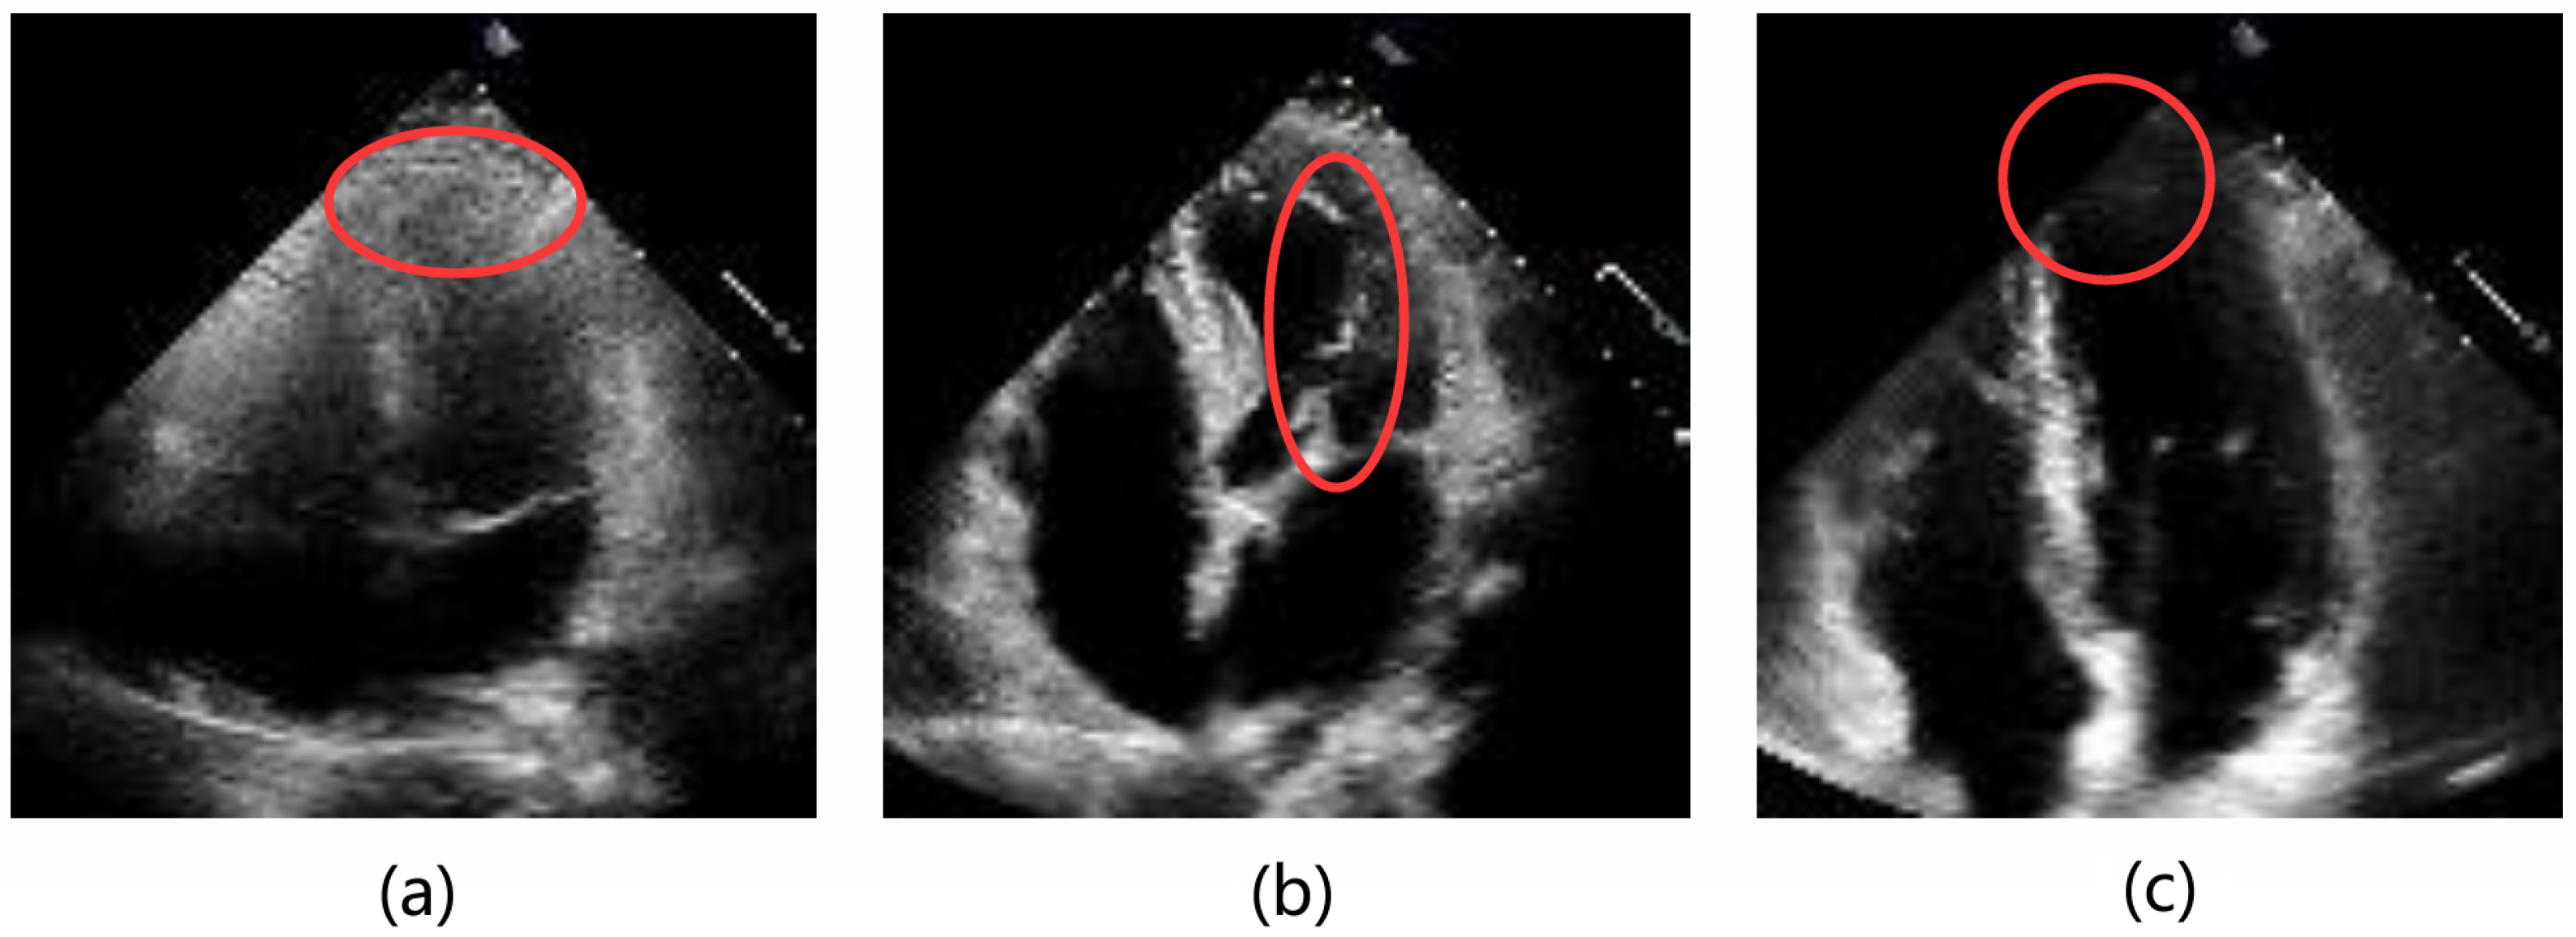

- We propose the Temporal Feature Fusion Module (TFFM) based on temporal–channel self-attention. It fuses the temporal and channel dimensions and applies self-attention to the fused dimension to capture the inter-frame correlations in echocardiography images. Additionally, we introduce a channel aggregation module that extracts complementary interaction information between channels to reallocate features of the fused channels. This module summarizes the features of multiple frames and enhances the features of ambiguous regions in key frames caused by noise and artifacts.